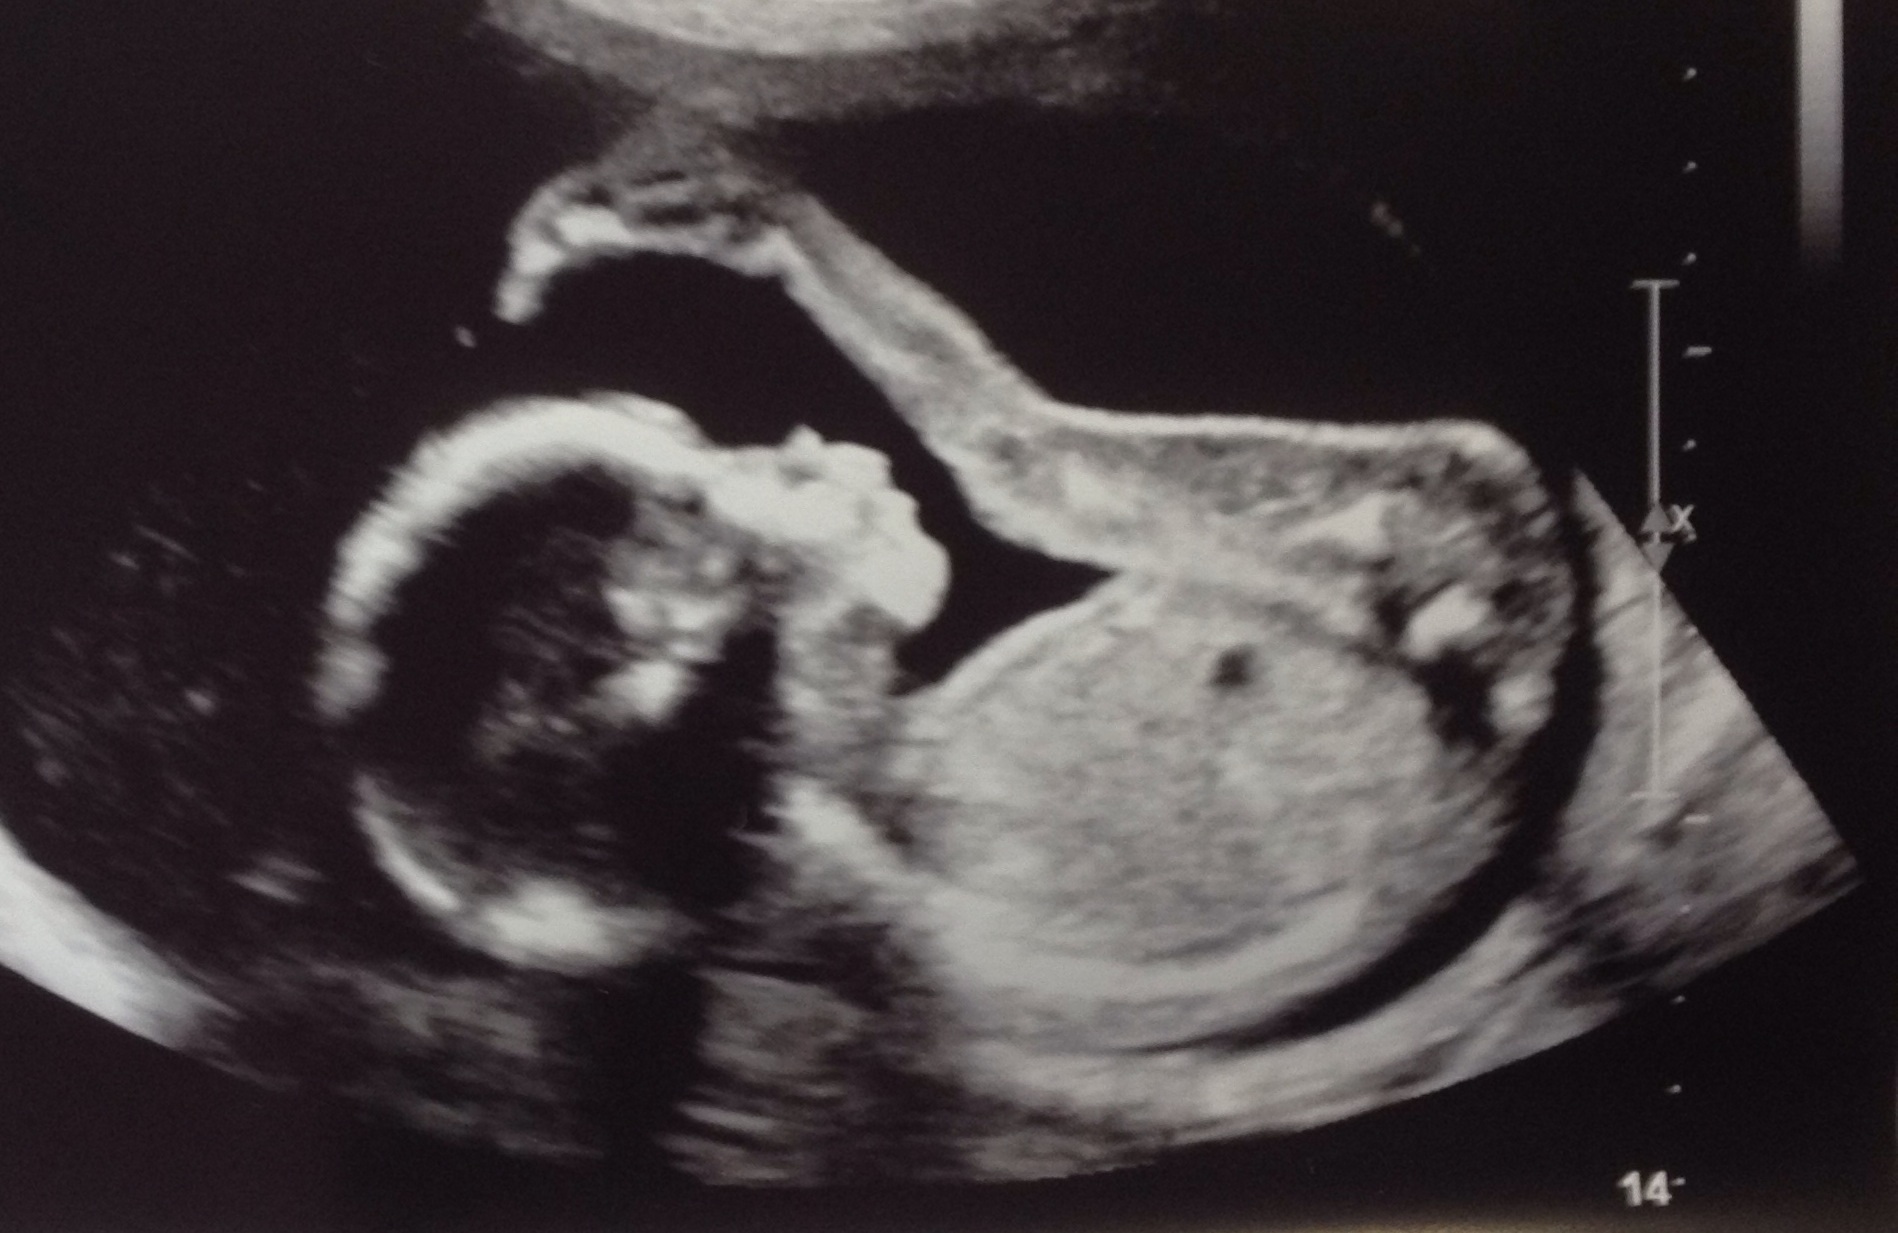

20 week scan pic....we are not finding out if boy/girl until birth, (so no potty shot I'm afraid!) but my curiosity would love to hear any guesses/intuition on gender. Thanks!